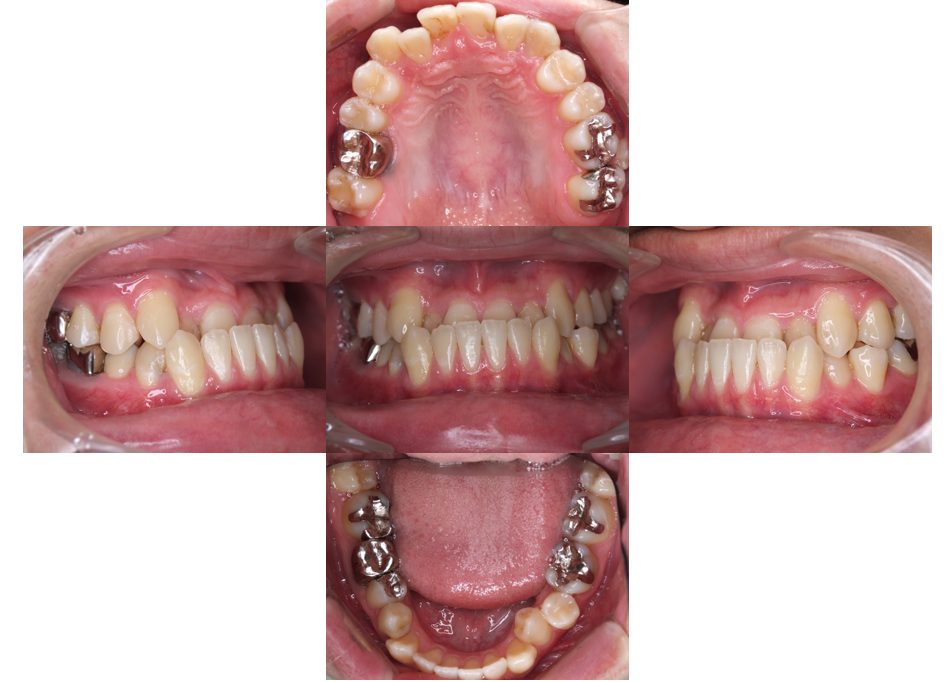

矯正治療・インプラント治療・セラミック治療の症例紹介(三隅歯科クリニック)

三隅 賢祐(三隅歯科クリニック)

症例詳細

| 主訴 | 30代女性 顎関節が痛い。見た目も気になる |

| 治療内容 | 矯正治療を行いました。 |

| 治療費 | 1,700,000円(税込み) |

| 治療期間 | 3年(矯正治療期間 2年半) |

| 治療回数 | 40回 |

| 想定されたリスク | 術前に精密な診査診断とシミュレーションを行い、インプラントを適正なポジションに埋入しておかないと、インプラント自体が矯正治療の邪魔になるリスクがあった。 |